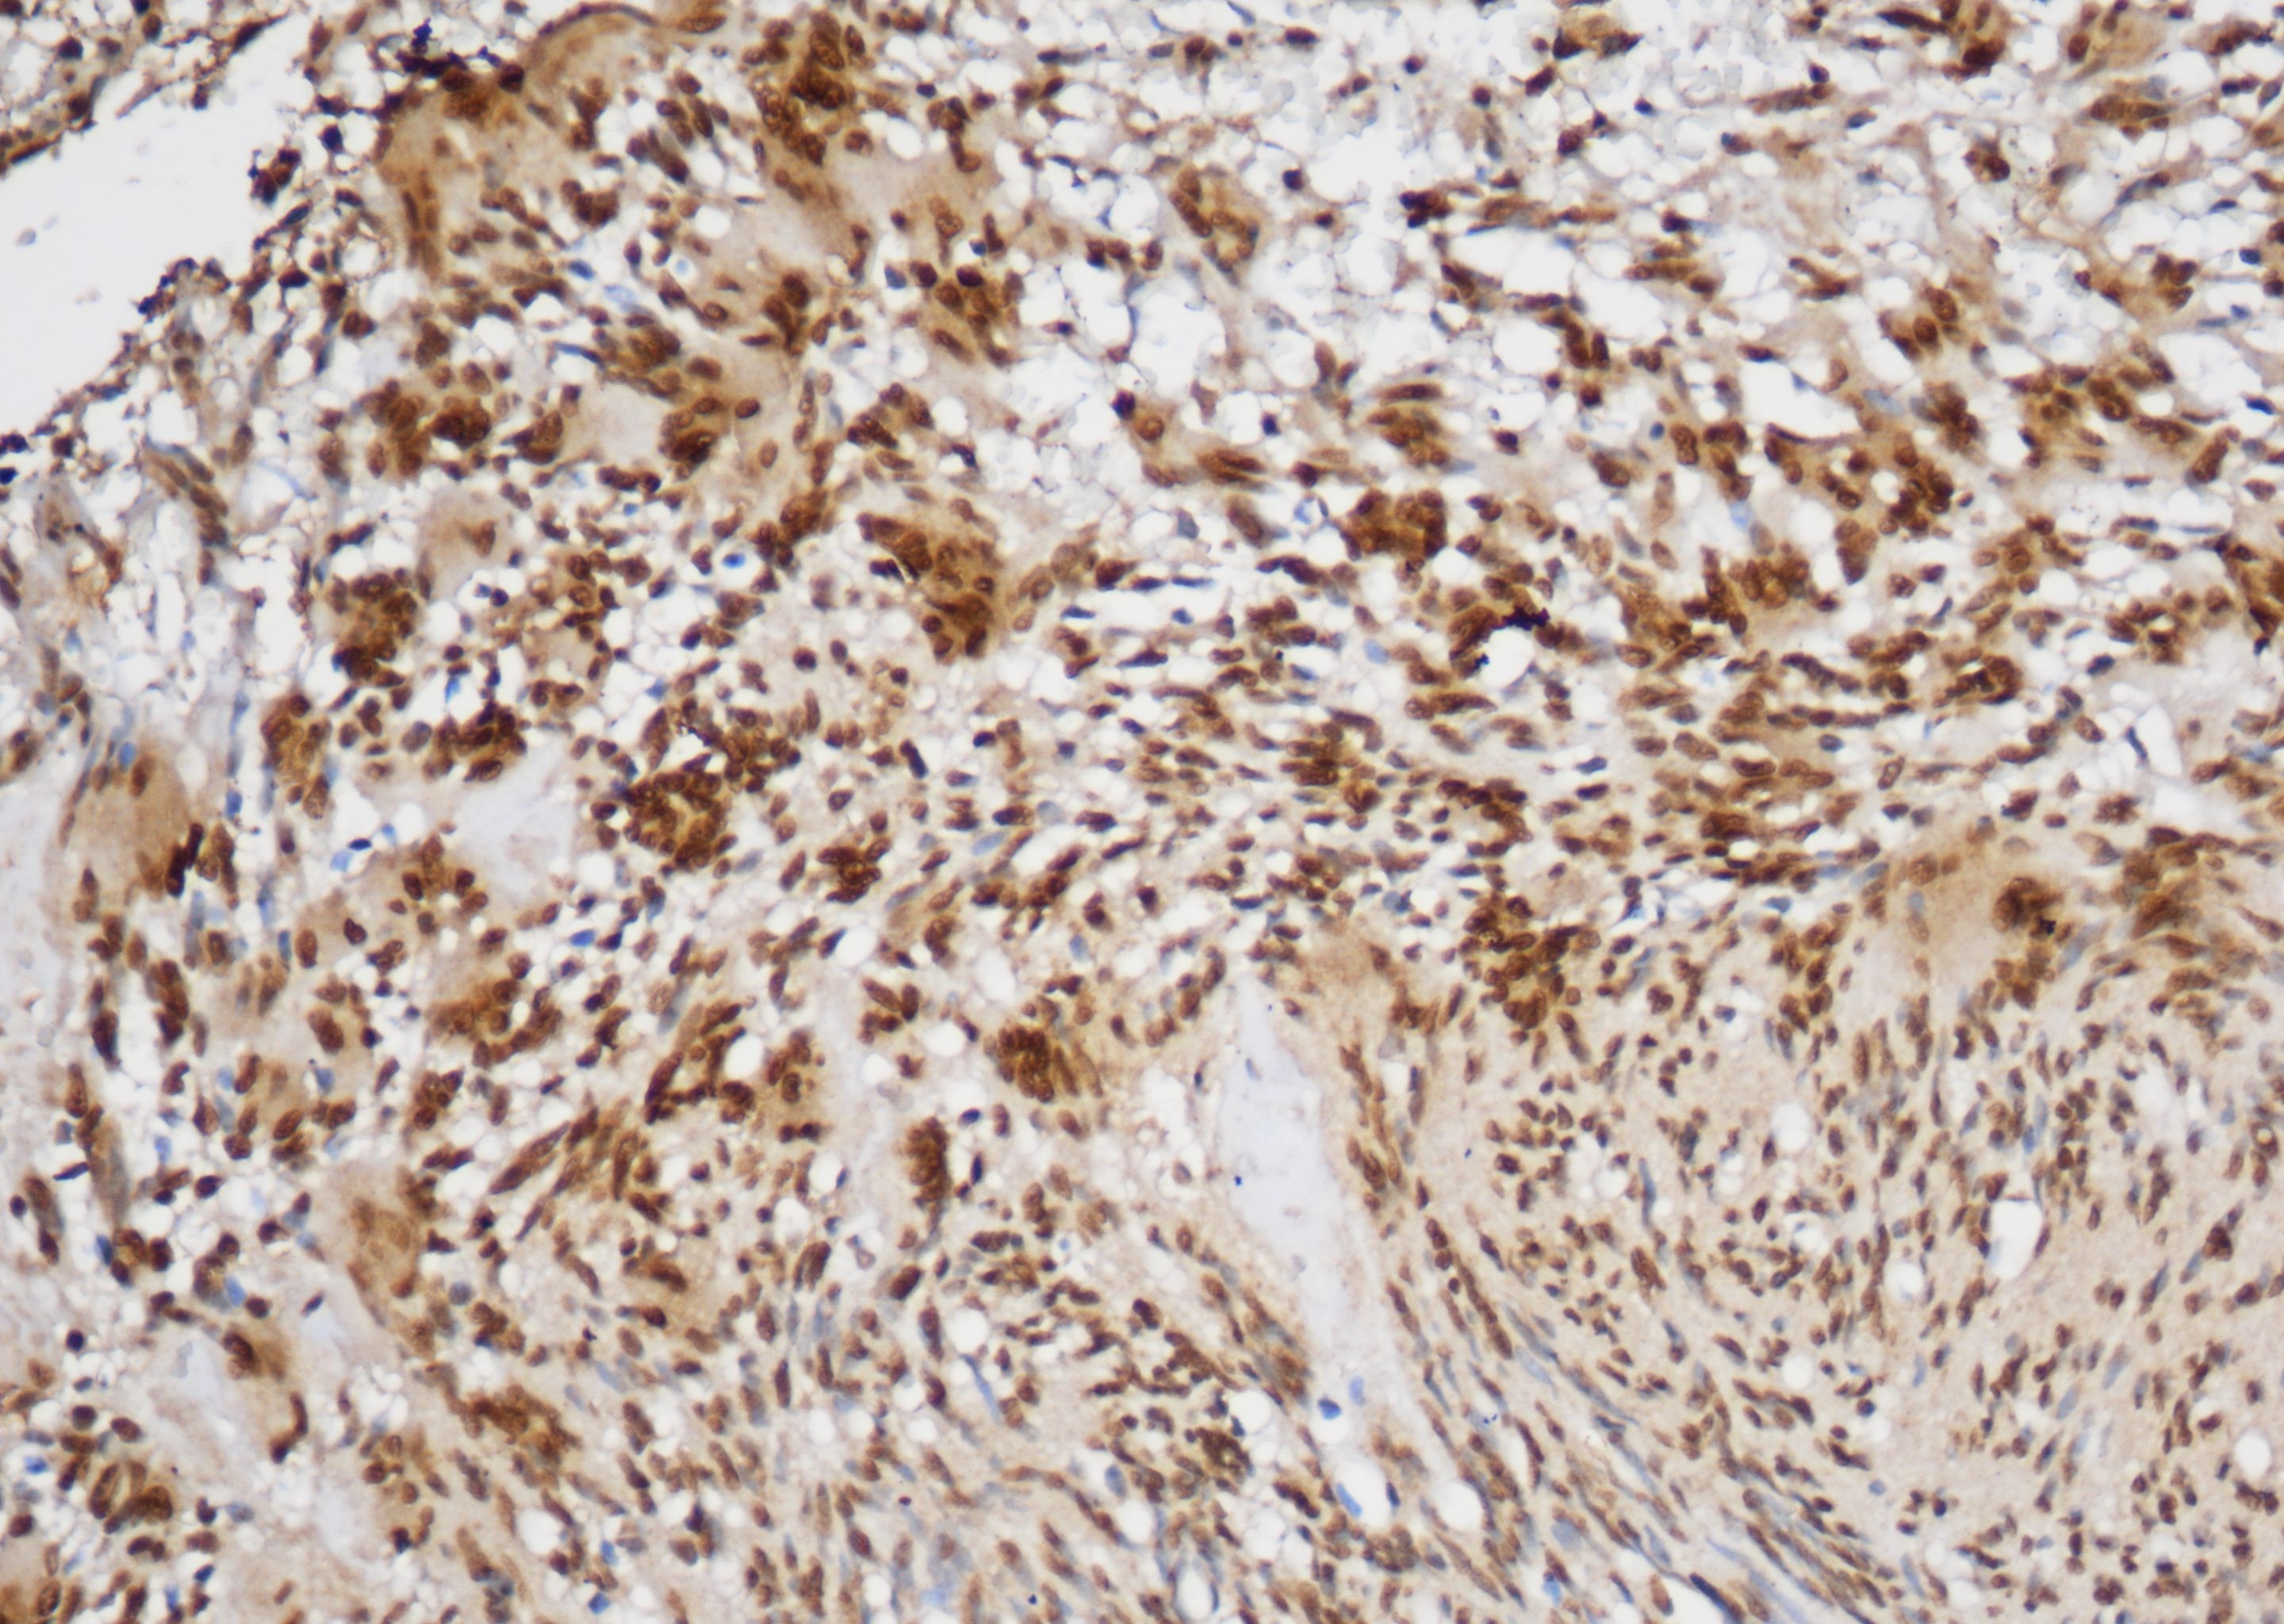

EMA(pithelial membrane antigen,上皮膜抗原)是一种高分子量的跨膜糖蛋白,广泛分布于各种上 皮细胞及其来源的肿瘤,可标记大部分正常上皮及上皮源性的肿瘤。EMA可用于间皮反应与间皮瘤,间皮瘤与腺癌,基底细胞、鳞状细胞与皮肤基底细胞癌,淋巴结ALK+的大细胞间变型淋巴瘤与其他淋巴瘤类型的鉴别。

| 细胞定位 | 细胞质/膜 |